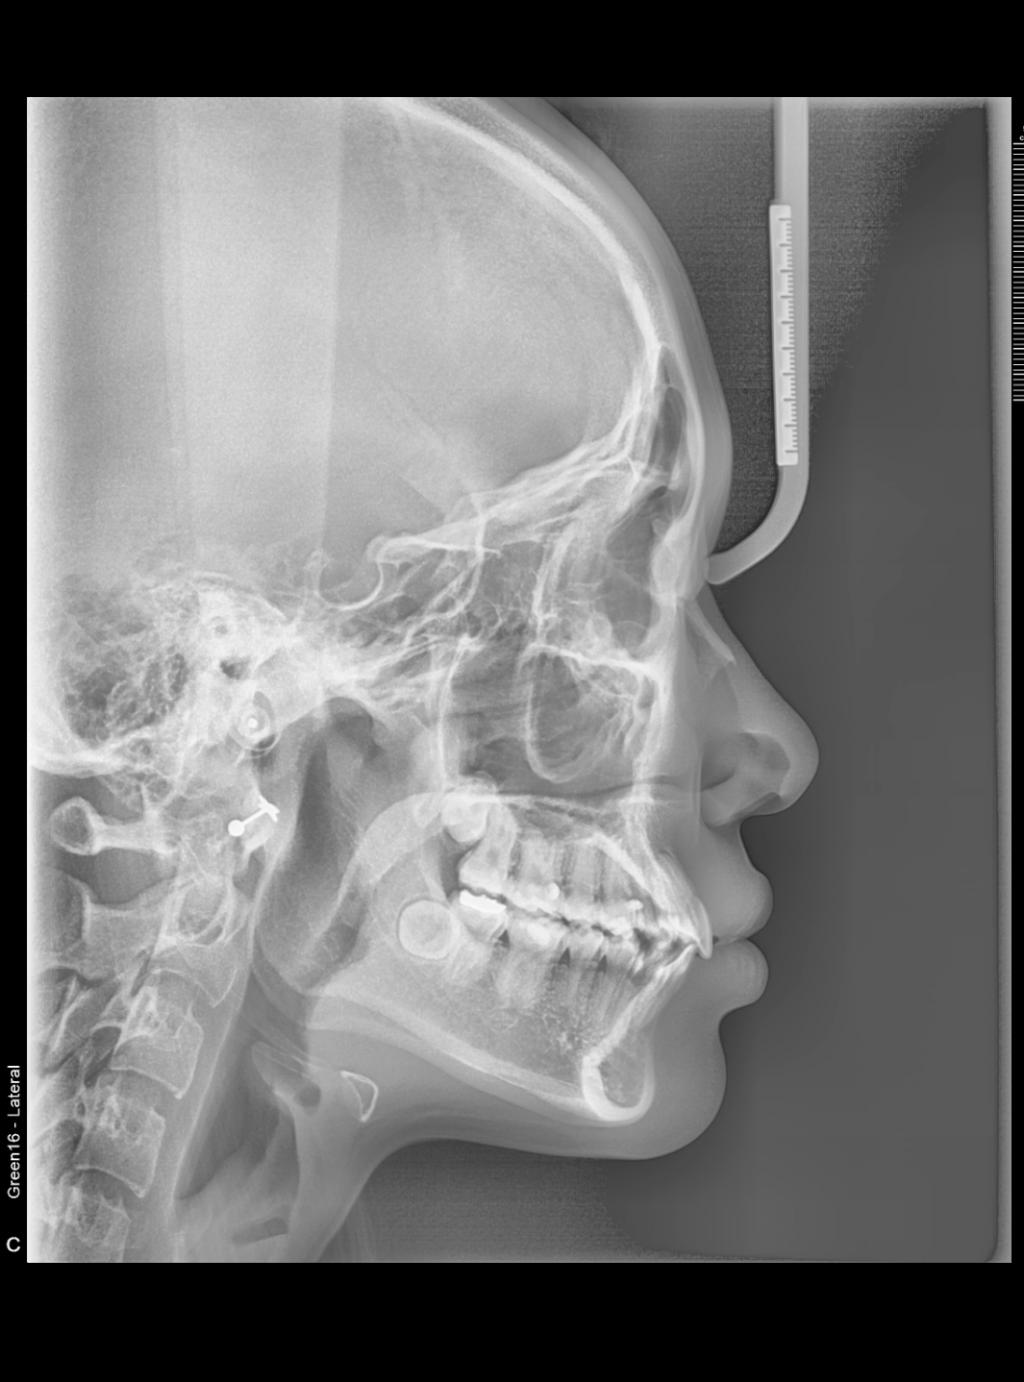

방사선 사진으로만 외모를 평가하기가 쉽지 않어서요.

또한 저희가 분석 할 때는 방사선 사진에 해부학적 지점을 여러게 잡아서 각도와 길이를 잰 후에 비교평가를 하는데 그런 것이 없어서 좀 힘들다는 것입니다.

우선 치료 전 후 방사선 사진을 비교 할 때 치료 후 방사선 사진에서 아래턱의 아래 골격선을 보면 약간 변형이 온 것 처럼 보입니다. 아무리 교정치료를 오래 받아도 이 선은 변화가 오지 않는데 변형된 것을 보면 방사선 사진을 찍을 때 잠깐 움직였던지 아니면 방사선 기계에 이상이 있었던 것 같습니다. 이로 인해서 아래턱의 연조직 선도 변형이 온것 같네요.

제 추측으로는 교정 전에 위 아래 앞니가 약간 겹쳐져 있었는데 교정치료를 비발치로 하기로 정하고 치료 하시면서 위 아래 앞니들이 약간 앞으로 나오지 않았나 생각합니다. 여기서 재교정 치료로 입이 들어가게 하시려면 아마도 발치를 해야할거 같네요. 치료 받으신 치과에 가셔서 다시 한번 상담을 받아 보시는게 좋겠습니다.